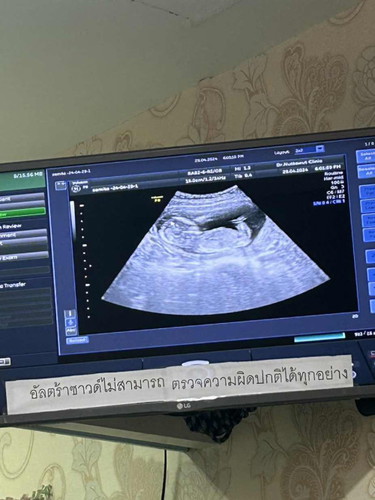

16สัปดาห์4วัน มีแม่บ้านไหนทราบเพศกันบ้างหรือยังค่ะ

ยังเลยค่ะ 16week พึ่งไปหาหมอมา หมอนัดซาวด์เพศอีกครั้ง 20weekค่ะ